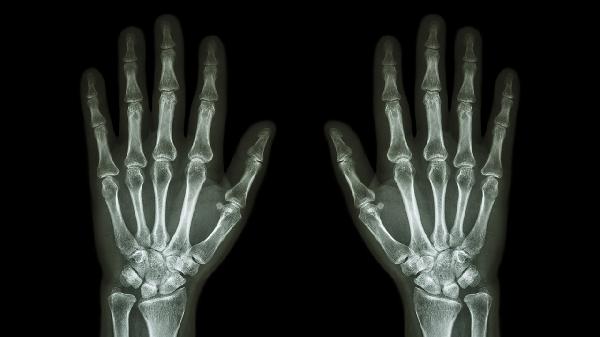

手指关节畸形可通过支具固定、药物治疗、物理治疗、注射治疗、手术矫正等方式改善。手指关节畸形可能与外伤、类风湿关节炎、骨关节炎、痛风性关节炎、先天性发育异常等因素有关,通常表现为关节肿胀、疼痛、活动受限等症状。

严重畸形需行关节成形术或融合术,如天鹅颈畸形矫正术、Boutonniere畸形修复术。术后需石膏固定4-6周,配合康复训练恢复功能。先天性畸形建议在骨骼发育成熟后手术。